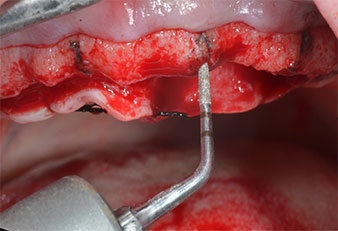

Un insert piézoélectrique diamanté de forme effilée (Piezomed I1) a été utilisé pour marquer les positions implantaires et effectuer la préparation pilote (Fig. 3). On a pris soin de travailler selon un mouvement ascendant et descendant, à puissance réduite, irrigation complète et basse pression (moins de 300g). Ensuite, un insert pilote (Piezomed I2A/I2P) a été utilisé pour l’agrandissement initial de 2mm du diamètre des sites implantaires (Fig. 4), suivi d’un insert de 3mm (Fig. 5).

En cas de densité osseuse élevée, il convient d’utiliser toute la gamme d’inserts, y compris les inserts intermédiaires Piezomed Z25P et Z35P afin d’élargir

les ostéotomies avant l’étape d'agrandissement suivante.

Dans le cas présent, les inserts Z25P et Z35P n’ont pas été utilisés car l’os postérieur était relativement mou

et l’intervention sur celui-ci a été aisée avec le I3A/I3P.

Compte tenu de la dureté relative de l’os (D2) à cet endroit, les sites recevant des implants de 10mm de long aux régions 11 et 21 ont été finalisés à l'aide d’une fraise de 4mm de diamètre, associée à un contre-angle chirurgical W&H WS-75 L, au moteur d'implantologie Implantmed de W&H ainsi qu’au module Osstell ISQ de W&H. En revanche, en raison de leur structure osseuse molle, les sites postérieurs ont été préparés en vue de l’obtention d’un diamètre final de 3mm à l'aide de l’insert Piezomed I3P. Les implants ont enfin été posés par voie transgingivale (Flap Less) pour obtenir l’ostéointégration dans un délai de trois mois (Figures 6-10). L'appareil existant a été maintenu sur quatre implants provisoires (Fig. 8).